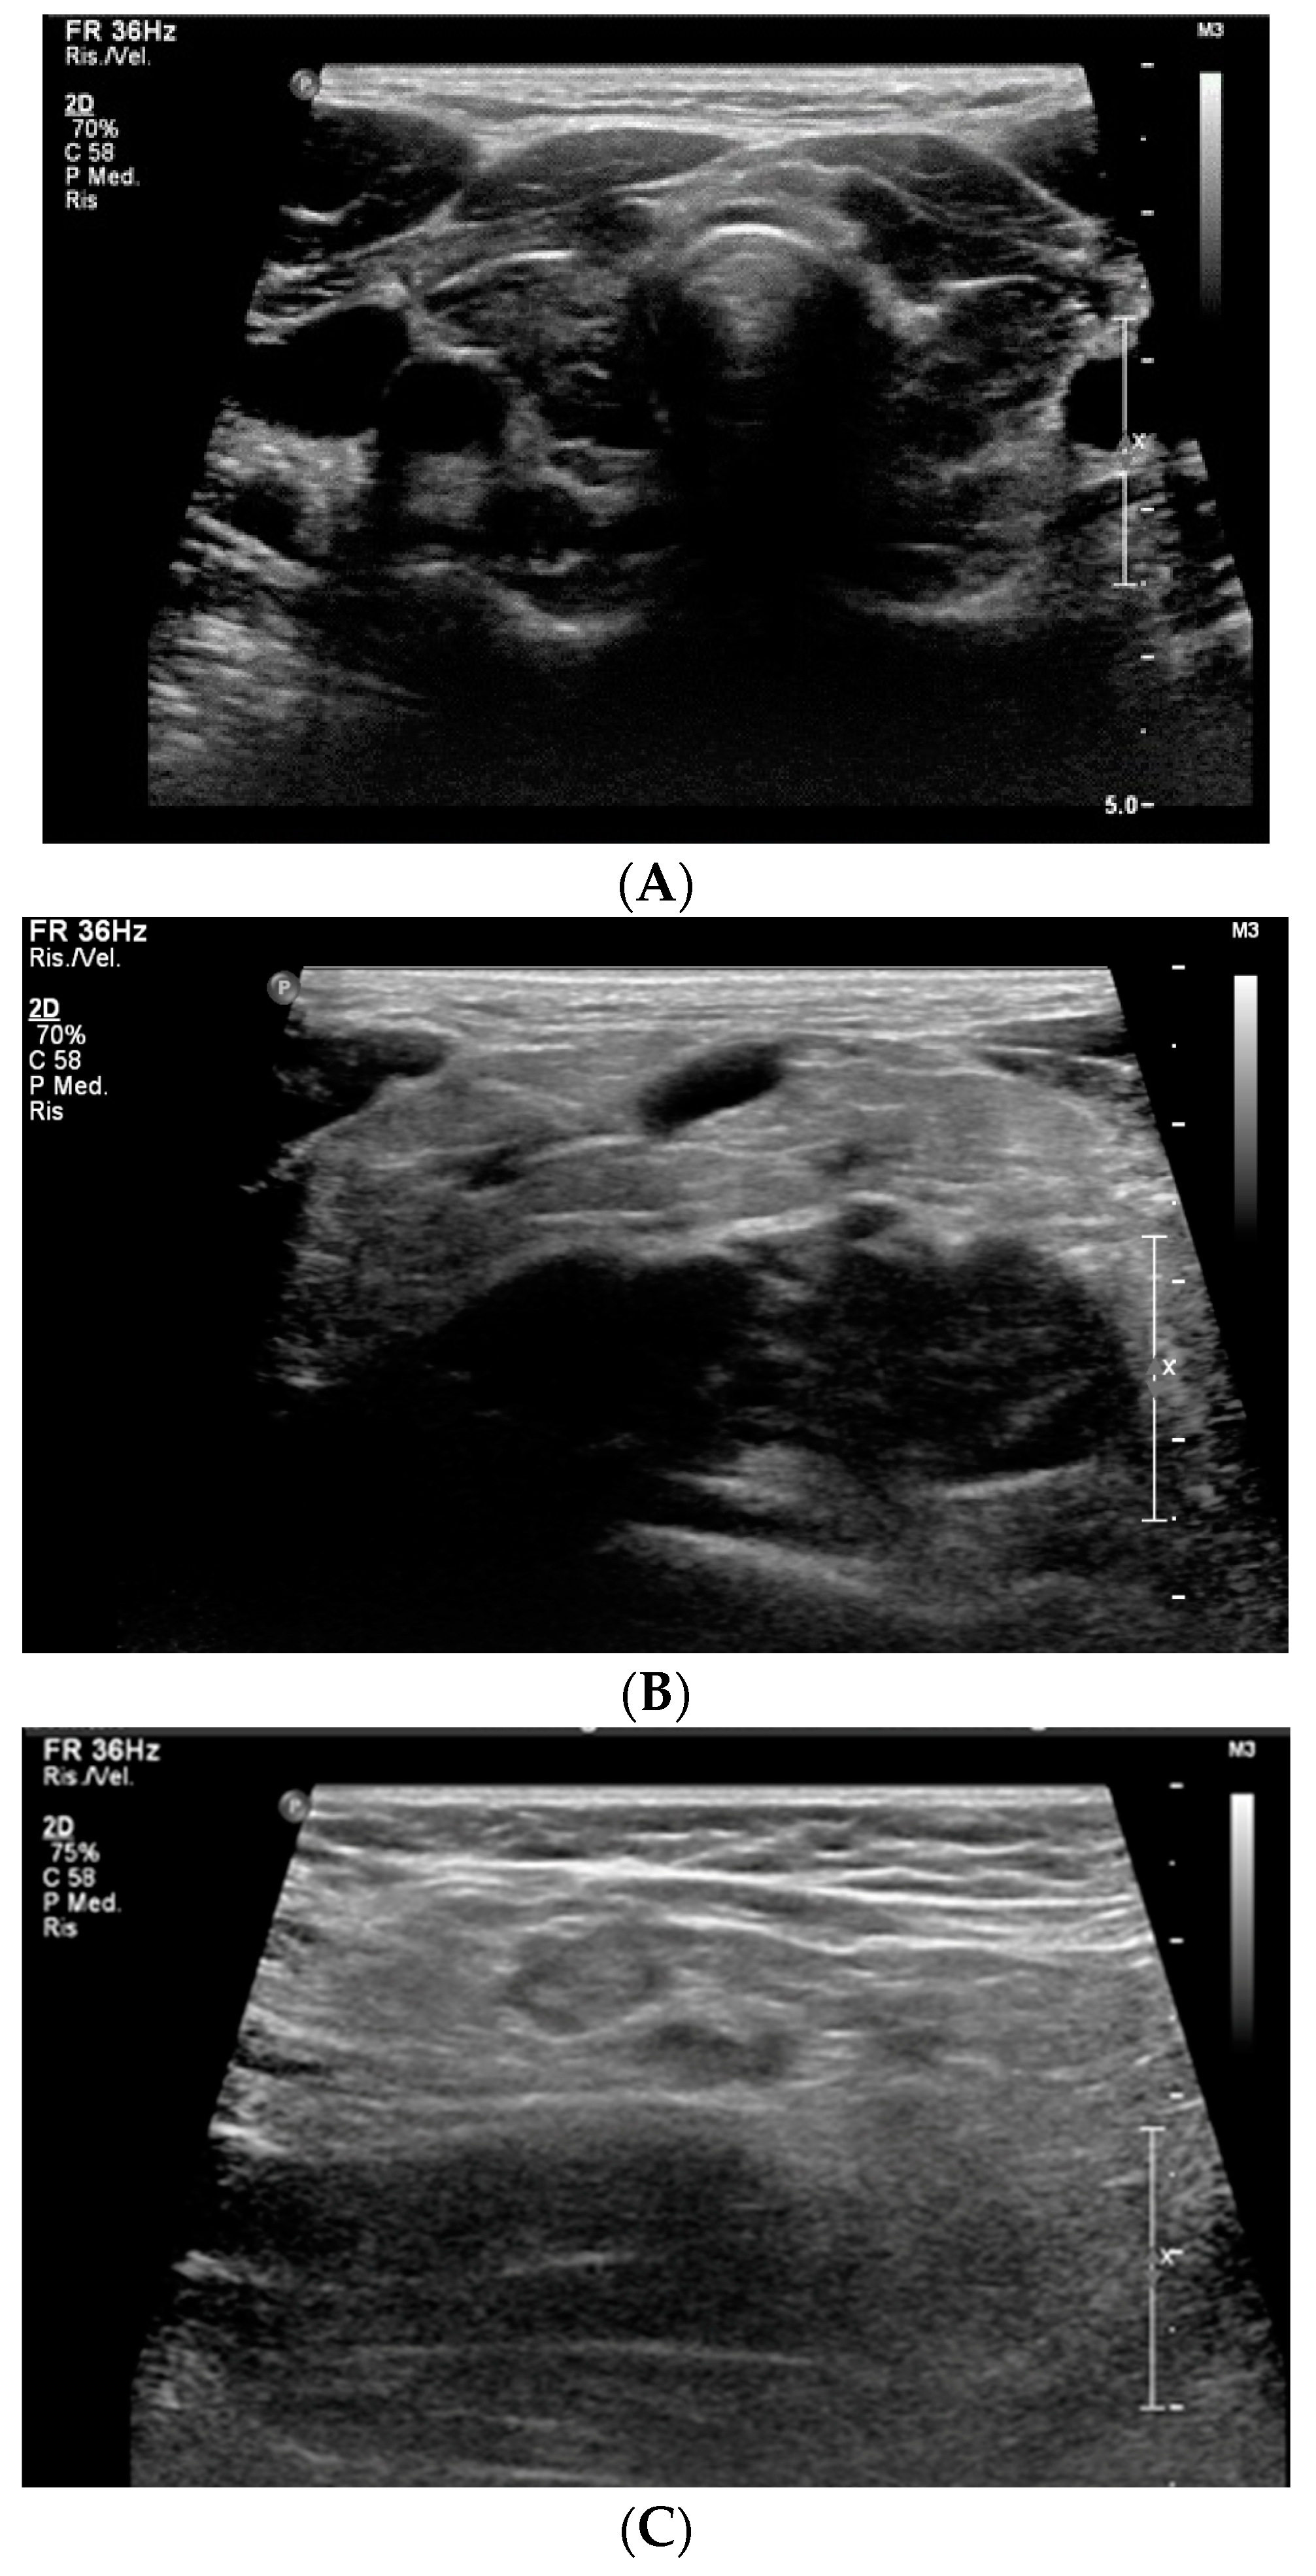

The US of thyroid and edematous soft tissues showed an enlarged thyroid gland, with heterogeneous echo structure, multiple hypoechoic foci, micronodular appearance and increased vascularization (consistent with thyroiditis), and thickening of subcutaneous adipose tissue, respectively (Figure 1A–C).

Figure 1. Ultrasound findings of thyroiditis (A), thickening and hyperechogenic of subcutaneous adipose tissue in the right supraclavicular region (B) and in the right armpit (C).